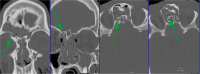

Fractures of the midface pose a serious medical problem as for their complexity, frequency and their socio-economic impact. Interdisciplinary approaches and up-to-date diagnostic and surgical techniques provide favorable results in the majority of cases though. Traffic accidents are the leading cause and male adults in their thirties are affected most often. Treatment algorithms for nasal bone fractures, maxillary and zygomatic fractures are widely agreed upon whereas trauma to the frontal sinus and the orbital apex are matter of current debate. Advances in endoscopic surgery and limitations of evidence based gain of knowledge are matters that are focused on in the corresponding chapter. As for the fractures of the frontal sinus a strong tendency towards minimized approaches can be seen. Obliteration and cranialization seem to decrease in numbers. Some critical remarks in terms of high dose methylprednisolone therapy for traumatic optic nerve injury seem to be appropriate. Intraoperative cone beam radiographs and preshaped titanium mesh implants for orbital reconstruction are new techniques and essential aspects in midface traumatology. Fractures of the anterior skull base with cerebrospinal fluid leaks show very promising results in endonasal endoscopic repair.